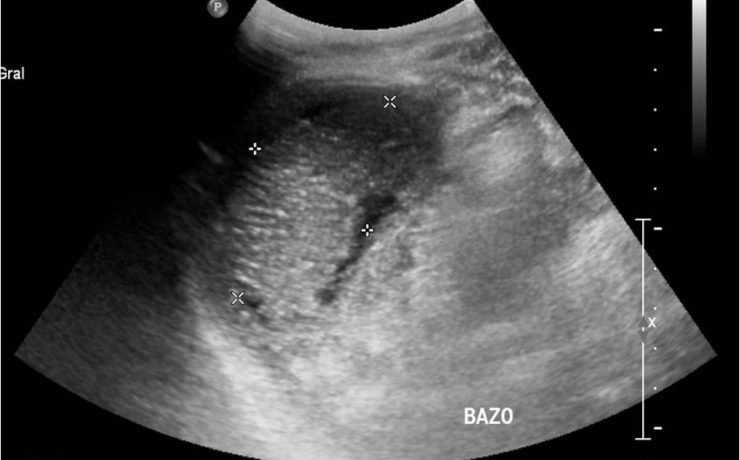

El incremento de la obesidad, del síndrome metabólico y su subsiguiente manifestación hepática, el hígado graso no alcohólico, se ha convertido en una enfermedad muy común en la práctica médica. El desarrollo de los conocimientos sobre el NASH se basa en la teoría inicial de los dos golpes o momentos.